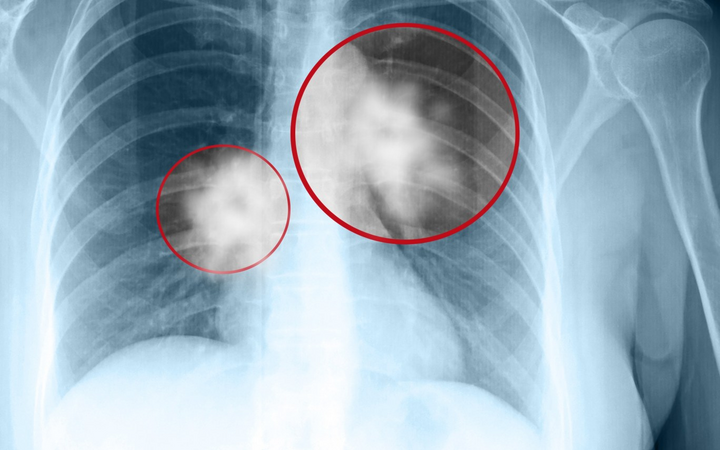

Theo Trung tâm Kiểm soát bệnh tật thành phố Hà Nội (CDC Hà Nội), trong tuần qua (từ ngày 16/5 đến ngày 23/5), thành phố ghi nhận 155 trường hợp mắc Covid-19, không có ca tử vong.

Cộng dồn từ đầu năm đến nay Hà Nội ghi nhận 192 trường hợp mắc Covid-19, không ghi nhận tử vong, số ca mắc giảm so với cùng kỳ năm 2024. Theo CDC Hà Nội, số ca mắc có xu hướng tăng trong 2 tuần gần đây, tiếp tục ghi nhận ca bệnh trong thời gian tới.